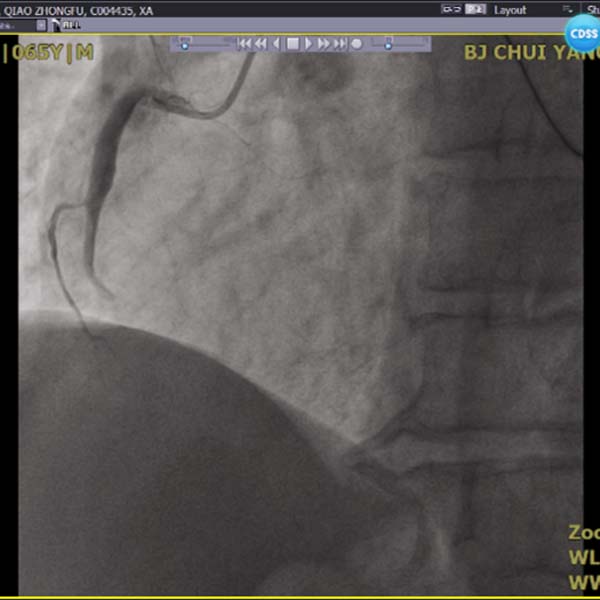

2022年1月2日,一名急性心梗患者经急诊介入治疗将右冠脉进行血栓抽吸后置入一枚支架,成功开通罪犯血管后,收入CCU病房。